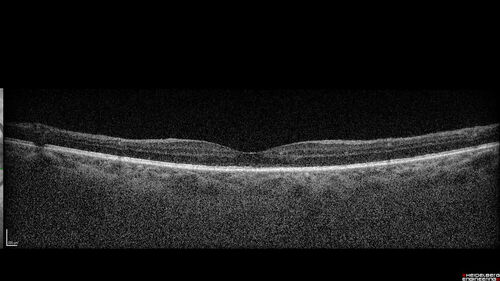

Syphilitic optic neuritis

Two weeks ago she woke up with blurred vision in the left eye.  She usually gets up at 5 AM.  Then she noticed a gray spot in the left eye that did not go away.  This is new for her.  The gray spot is not getting any better or worse in the left eye. (4/4/23)

VA OD: sc20/80 PH20/50 NscJ10

VA OS: sc2'/200 Nsc20/400

IOP: TP: OD:15 OS:16

No AC or vitreous cells - later images was with second eye involved with uveitis.  Patient received IV PCN and was lost to follow-up